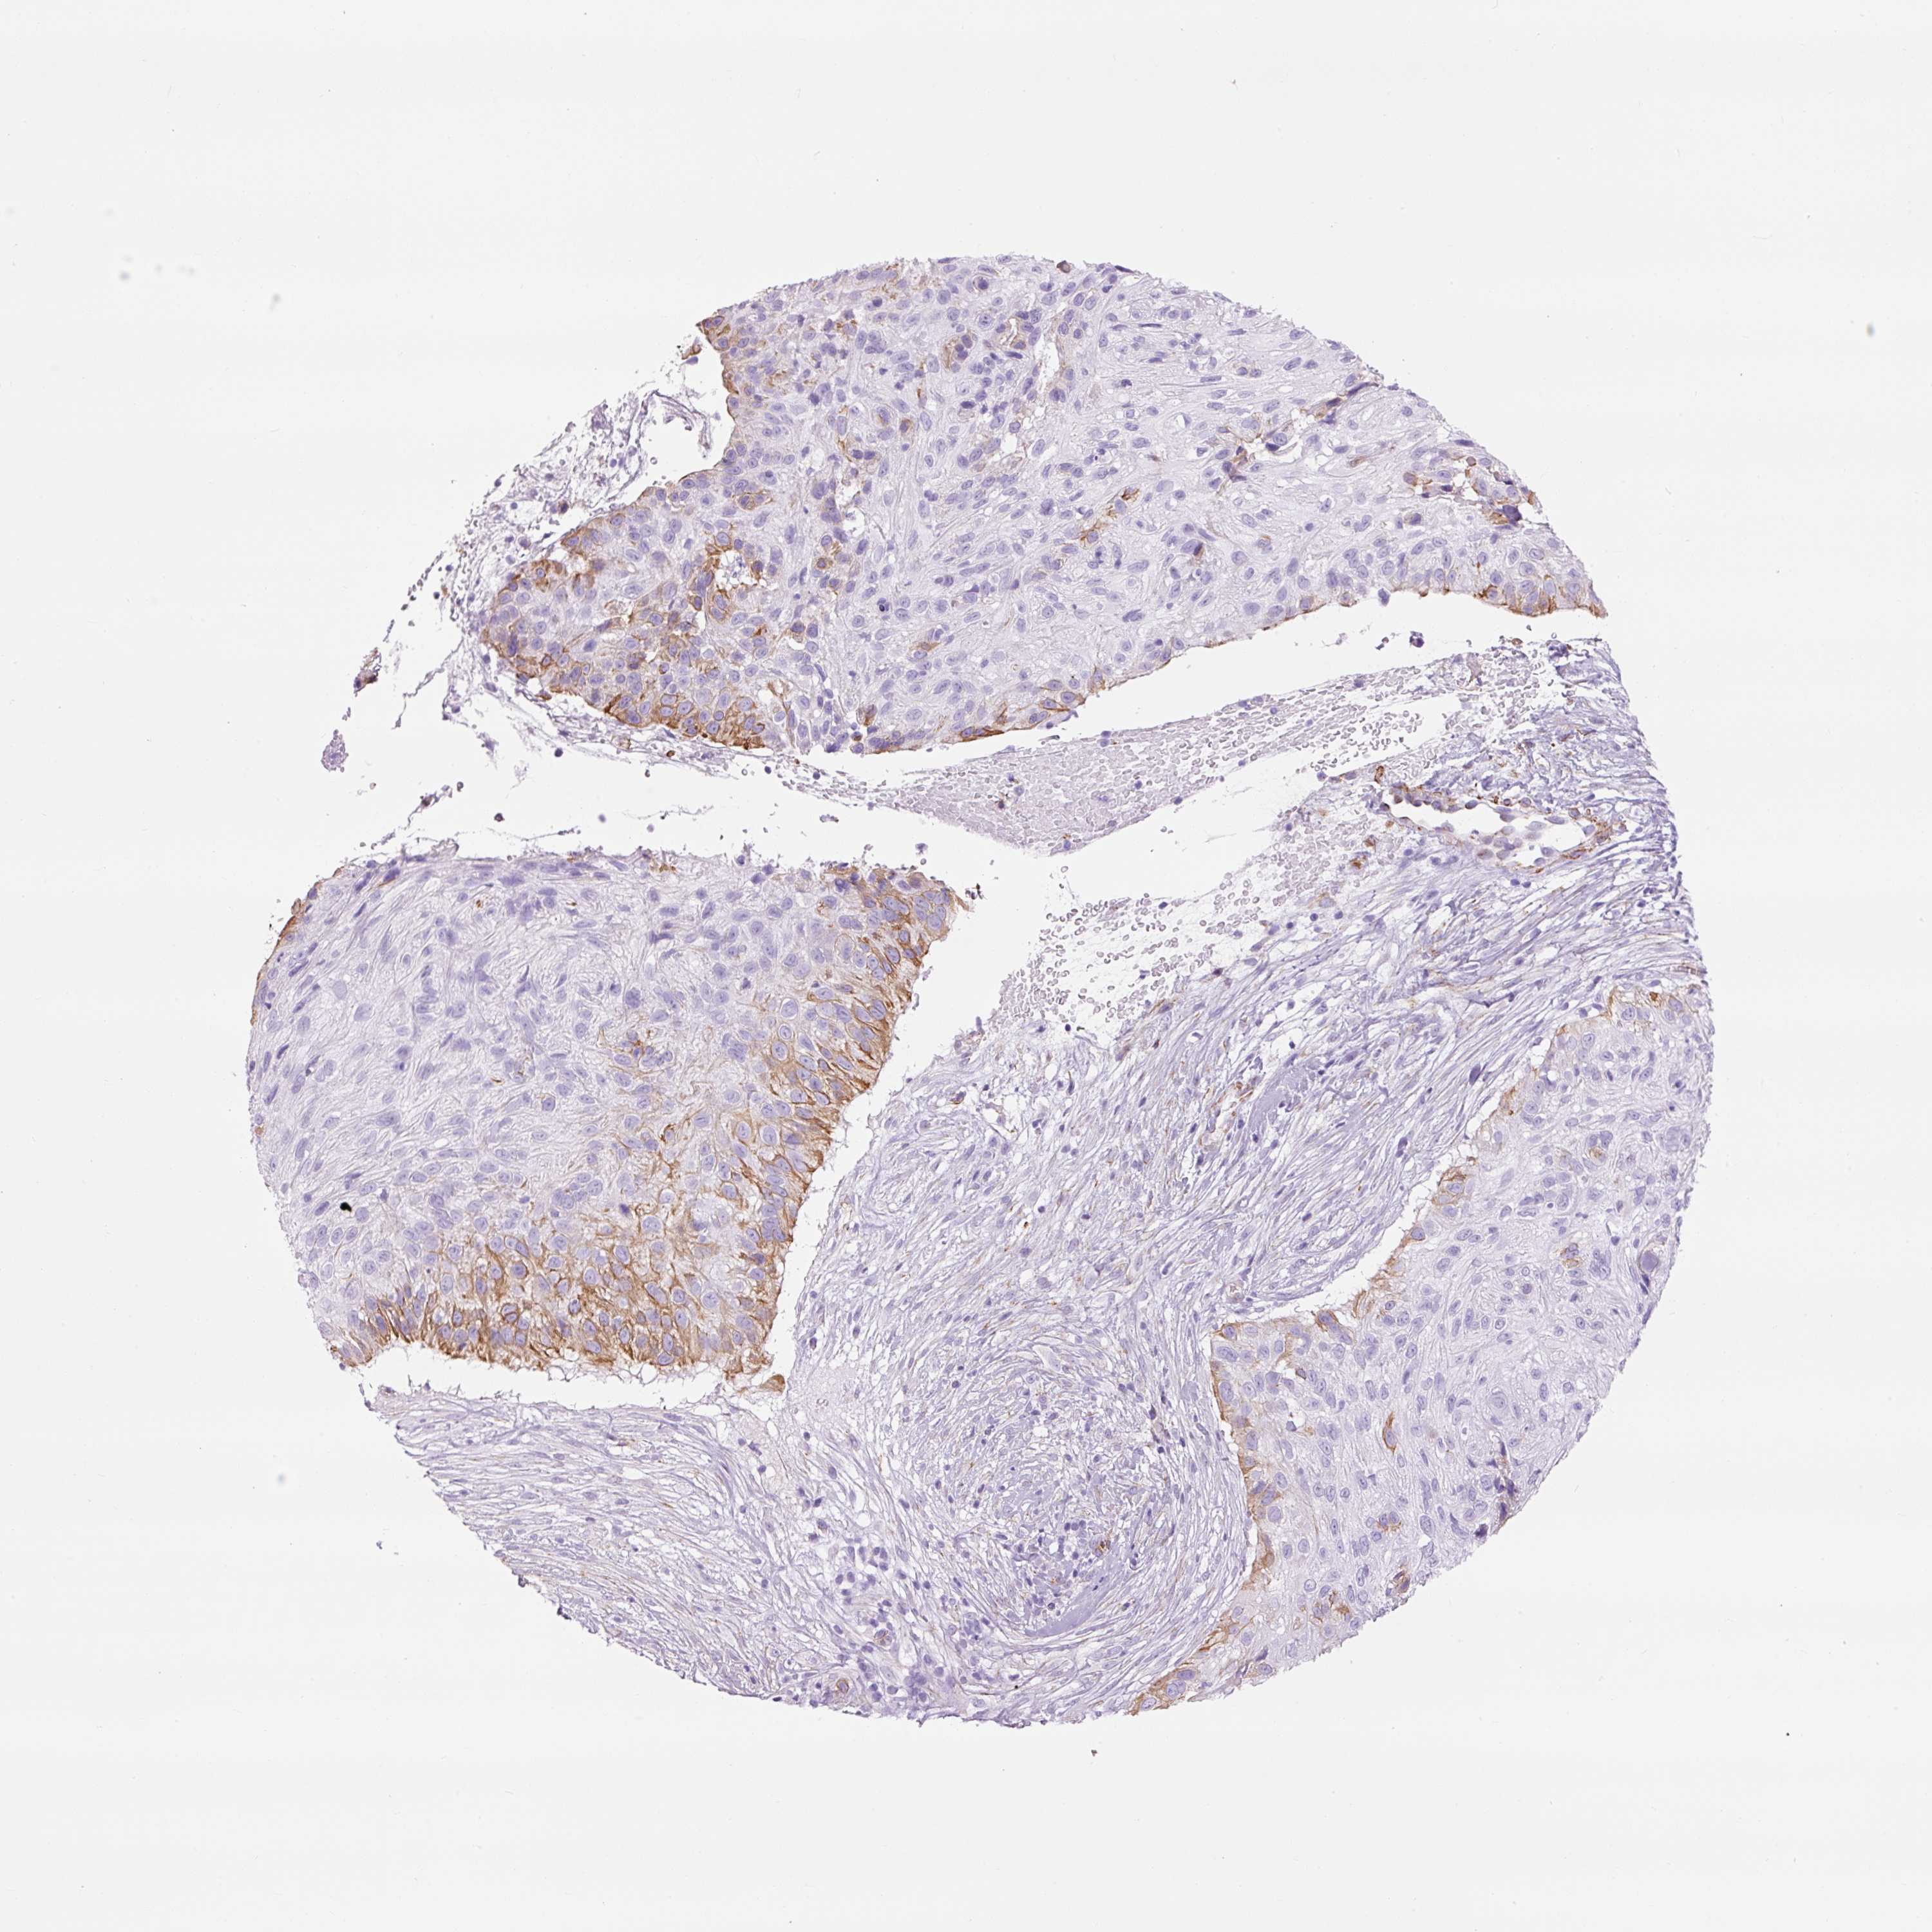

SKIN CANCER - Protein expressioni

A mouse-over function shows sample information and annotation data. Click on an image to view it in a full screen mode. Samples can be filtered based on level of antibody staining by selecting one or several of the following categories: high, medium, low and not detected. The assay and annotation is described here.

Antibody stainingi

Antibody staining in the annotated cell types in the current human tissue is reported as not detected, low, medium, or high, based on conventional immunohistochemistry profiling in selected tissues. This score is based on the combination of the staining intensity and fraction of stained cells.

Each image is clickable and will lead to virtual microscopy that enables deeper exploration of all samples and also displays staining intensity scores, fraction scores and subcellular localization as well as patient and tissue information for each sample.

Antibody HPA049326

Antibody CAB003791

Basal cell carcinoma

Squamous cell carcinoma, NOS